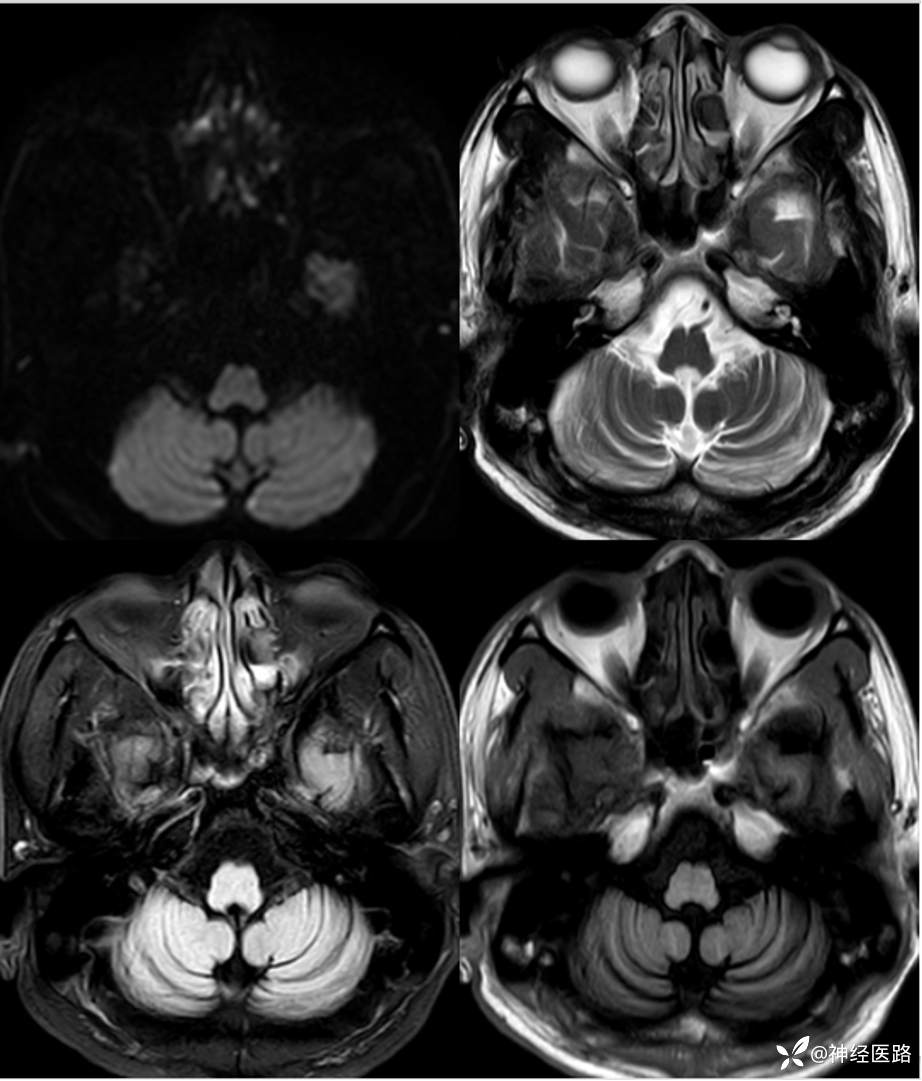

辅助检查:头部磁共振:1.颅脑DWI未见明显异常扩散受限。 2.脑白质高信号,脑萎缩。3.双侧上颌窦、双侧筛窦、双侧额窦炎。

两次影像对比